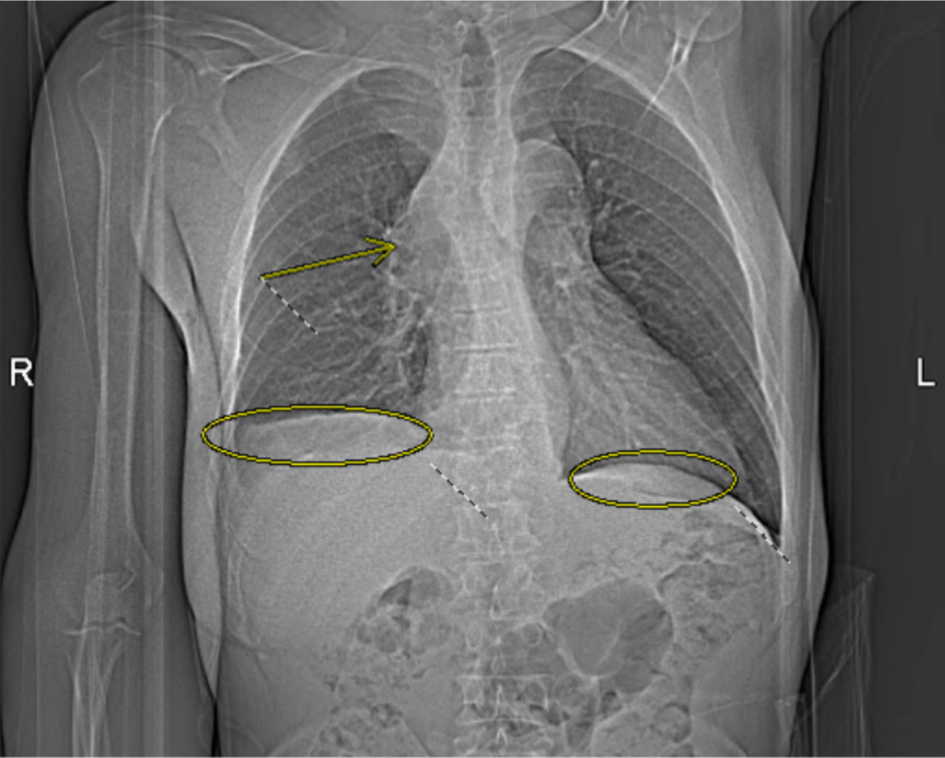

Upon physical examination, the patient appeared to have distended upper chest veins, bilateral upper extremity swelling (more on right side), rales (oxygen saturation was 99% on room air), and mild facial swelling. Lab results displayed the patient being anemic with a hemoglobin of 11.4 g/dL (normal: 14.0–17.5 g/dL), elevated white blood cell count (WBC) level of 13.8 cells/µL (normal: 4.0–11.0 × 103/µL), eosinophils of 11% (normal: 0–5%), and an elevated platelet count of 447,000/µL (normal: 150–400 × 103/µL). The differential diagnosis included: DVT of the upper extremity, SVC syndrome, lymphedema exacerbation, primary lung cancer, lymphoma, and infection. In view of the patient’s history of DVT, an initial duplex ultrasound was ordered to rule out acute DVTs. Furthermore, a computed tomography angiography (CTA) pulmonary series was conducted which revealed bilateral pleural effusions, moderate pericardial effusions, and a large mediastinal mass causing severe SVC compression and right upper lobe pulmonary artery obstruction (Fig. 1). Notably, patient was also seen in the emergency department a few months prior, and chest X-ray revealed no abnormalities at the time.

Click for large image

Figure 1. Computed tomography angiography (CTA) pulmonary chest X-ray obtained on the day of admission demonstrates bilateral pleural effusions (circled) and a mediastinal mass causing severe superior vena cava (SVC) compression and right upper lobe pulmonary artery obstruction (arrow).